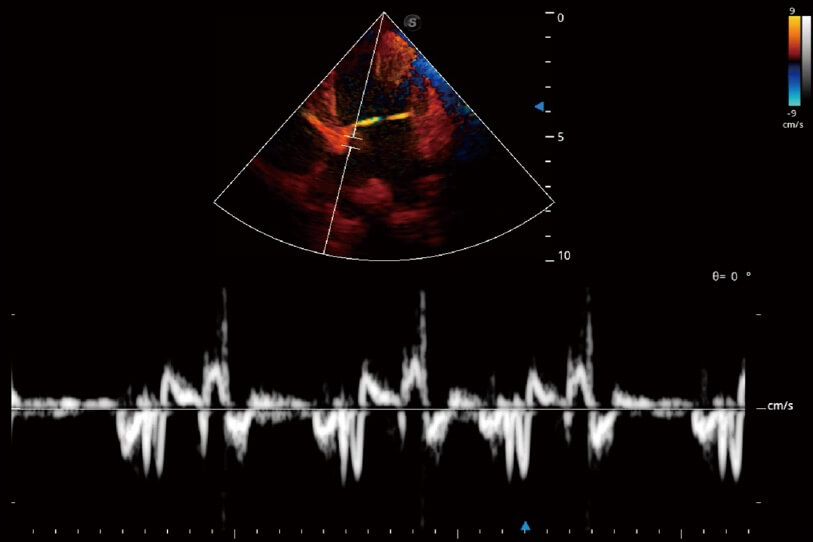

實(shí)時用顏色表示心肌組織運(yùn)動,觀察和定量組織的運(yùn)動情況,對快速檢測與評估心肌的灌注和活性、電傳導(dǎo)及心肌收縮和舒張功能等均能提供重要的診斷信息。